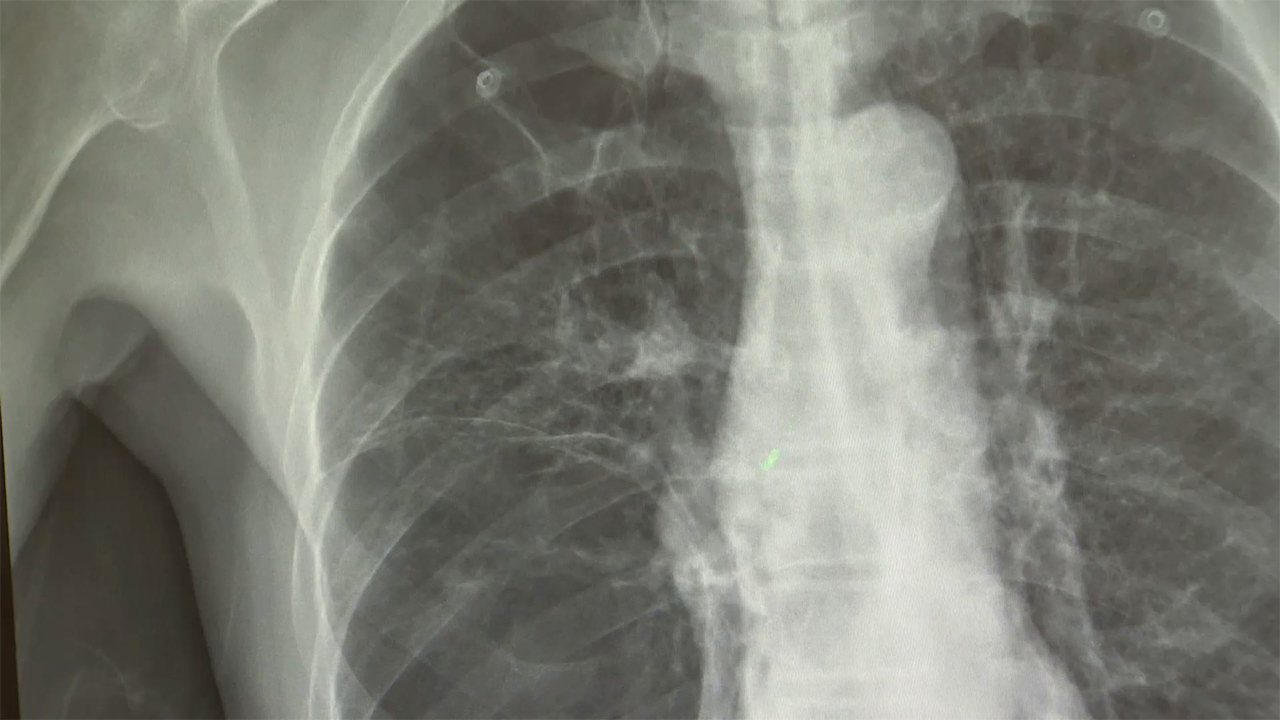

▲ 폐암 X-RAY

(사진=연합뉴스)